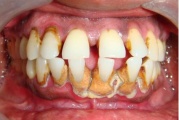

Krooniline parodontiit

Krooniline parodontiit on mikroobide poolt põhjustatud hammaste tugikudede põletik, mille tulemusena tekib progresseeruv alveolaarluu (nähtav röntgenograamil) ja periodontaalligamendi destruktsioon, igemetaskute moodustumine, igeme retsessioon või mõlemad kahjustused kombineeritult. Loe edasi »

Sümptomid:

- igemed veritsevad (19)

- igemed punetavad (21)

- ige on paistes (mädapunn)

- igemed on tursunud/vohavad (17)

- igemed on valulikud (19)

- igemepiir on taandunud (3)

- luu destruktsioon (5)

- puudulik suuhügieen (5)

- igemepealne hambakivi (5)

- igemealune hambakivi (4)